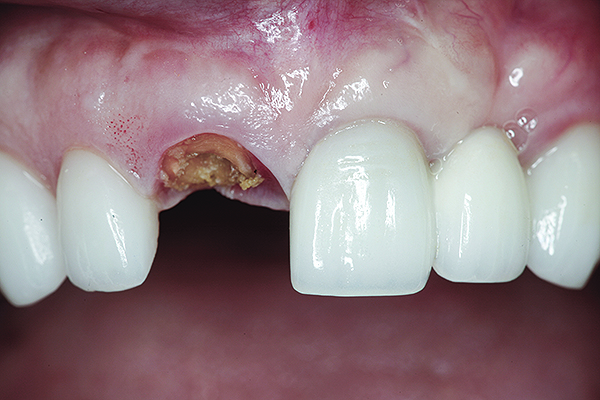

A 63-year-old female patient presented with mobility of her right maxillary incisor, tooth No. 8, secondary to endodontic therapy (Figure 1). Her medical and dental histories were non-contributory. Clinical and radiographic evaluations revealed an 8-mm probing depth on the palatal aspect. The tooth was deemed to be fractured (Figure 2). The treatment plan accepted by the patient was for extraction, immediate implant placement, and immediate provisional restoration, if possible.

Fig 3. The root tip, after removal of the crown.

Figure 3

Fig 4. The root was atraumatically extracted using periotomes.

Figure 4